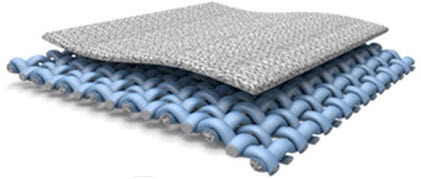

‘Heart on a chip’ reduces time and cost in drug testing for safety and efficacy

Replaces animal models, which have a high failure rate in predicting human reactions to new drugs